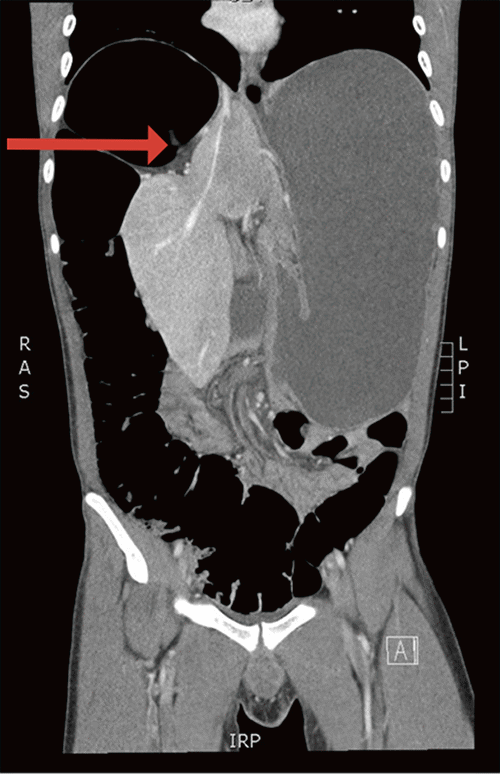

Figure 3. Coronal CT Scan on Second Presentation. Published with Permission

Distension of the colon and stomach with medial displacement of the liver (arrow)

During his second admission, CT demonstrated a diffusely distended gastrointestinal tract from the esophagus through the rectosigmoid colon (Figure 3). Due to the global gastrointestinal (GI) tract distension, suspicion increased for a GI motility disorder. Anorectal manometry, smart pill testing, autoimmune workup, and additional laboratory and genetic testing, however, were all normal. Final pathology of the previous rectal biopsy demonstrated ganglion cells, ruling out Hirschsprung disease. The patient lacked an etiology for Ogilvie syndrome. Upper endoscopy, notably performed after colonic decompression, did not show evidence of gastroduodenal obstruction. Exploratory surgery was offered, but without a clear diagnosis or definitive surgical plan, the patient declined. During both admissions, a CT scan was obtained after decompression, and the GI tract appeared normal. The patient ultimately recovered uneventfully during both admissions and was discharged.